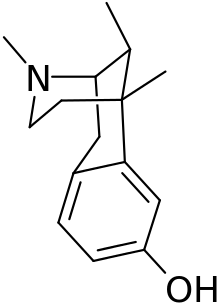

There are a number of broad classes of opioids:[260]

- Fully synthetic opioids: such as fentanyl, pethidine, levorphanol, methadone, tramadol, tapentadol, and dextropropoxyphene;

Morphinan derivatives

- Butorphanol—agonist/antagonist

- Nalbuphine—agonist/antagonist

- Levorphanol

- Levomethorphan

- Racemethorphan